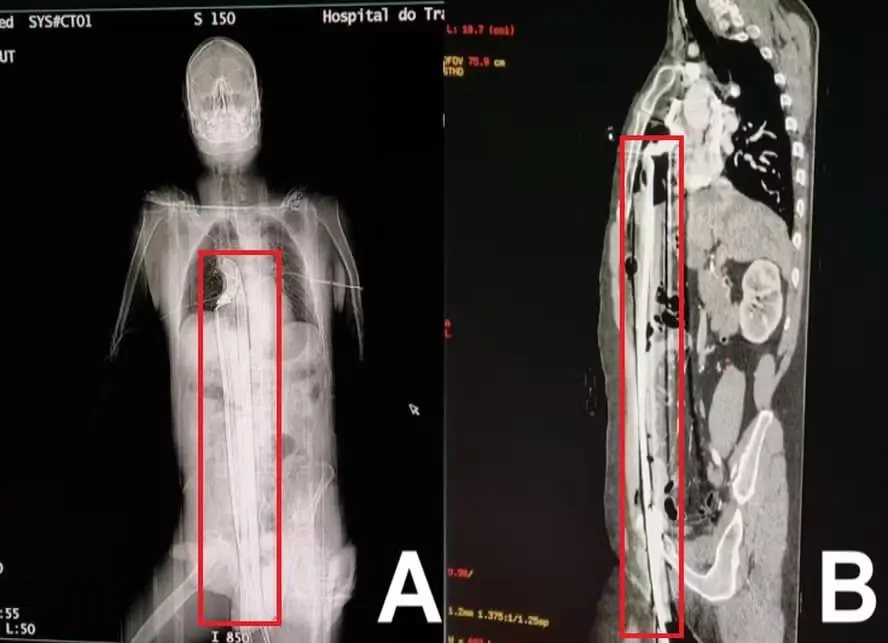

Imagens da barra de ferro atravessando o corpo do homem — Foto: Reprodução

O atendimento ocorreu no Hospital do Trabalhador, em Curitiba, e chamou atenção pela área delicada onde o objeto perfurou o corpo do homem. A barra de ferro atravessou seu fígado e atingiu o topo do diafragma, errando por pouco o coração.

Na publicação, os médicos revelaram que o homem precisou passar por uma complexa cirurgia para escapar, não desenvolveu problemas a longo prazo e teve alta em apenas três dias. Chegando ao hospital, o homem foi levado às pressas para uma cirurgia de emergência de esternotomia – onde o esterno é cortado e dividido para alcançar a barra de ferro.